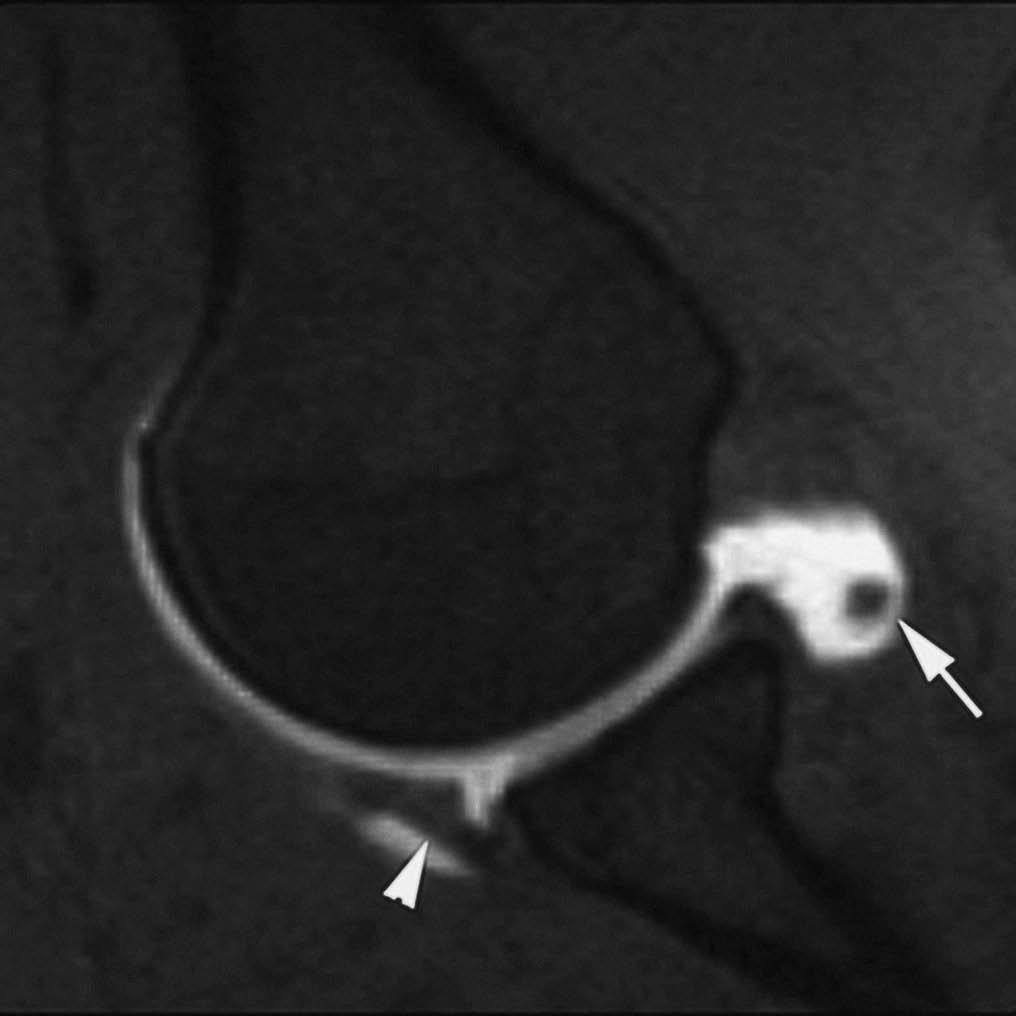

En la actualidad, la RMA es el método más eficaz en la valoración de las lesiones ligamentosas del tobillo. En la fase aguda, su indicación está limitada a aquellos casos en los que el cirujano plantea la realización de una reparación primaria --casos con lesión ligamentosa doble o en deportistas de alta competición--. Sin embargo, su principal indicación es la evaluación de la inestabilidad crónica de tobillo --tiene una sensibilidad del 100% y del 90% para las lesiones crónicas del LPAA y LPC, respectivamente (fig. 9), frente a una sensibilidad del 50% de la RM convencional--20,21.

Fig. 10.--Síndrome de choque antero-lateral. Corte axial de RMA potenciado en T1 que muestra un tejido fibroso irregular ocupando el receso capsular antero-lateral (flechas).